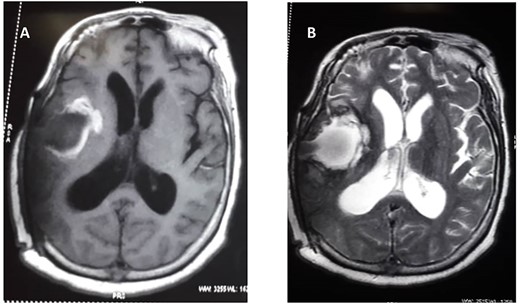

Cranial magnetic resonance image (MRI) revealed a large heterogeneous solid mass with multiple cystic areas in the right parietal lobe; this was associated with marked mass effect (Fig. 1A and B). The total brain lesion measured 7.2 × 6.0 × 7.3 cm, with the solid lateral component measuring 2.9 × 2.8 × 4.1 cm. There was heterogeneous contrast enhancement with extensive perilesional oedema. Magnetic resonance spectroscopy revealed decrease N-acetyl aspartate, creatinine and myoinositol and markedly increased lactate (Fig. 1C).

(A) Preoperative T1 weight. (B) T2-weighted MRIs. (C) Preoperative magnetic resonance spectroscopy.

She subsequently had right frontotemporal craniotomy and tumour excision. Intraoperative findings were those of a mixed consistency mass, which was firm, gritty with areas of necrosis and brown coloured cystic components. Histopathological examination of the tumour revealed neoplastic papillary structures infiltrating a dense fibro-collagenous matrix. The neoplastic papillae showed discohesive cells lining delicate fibrovascular cores; the cells exhibited marked nuclear pleomorphism with hyperchromatic and vesicular nuclei. Some abnormal mitotic figures were also seen and there were no residual neural tissues present (Fig. 2A–C). The overall histopathological features were consistent with papillary meningioma (World Health Organization Grade III). The MRI at 3 months post-operative showed gross total tumour resection with an area of cystic cavitation because of encephalomalacia from the previous tumour and surgery (Fig. 3A and B). She subsequently had adjuvant radiotherapy and was lost to follow-up.